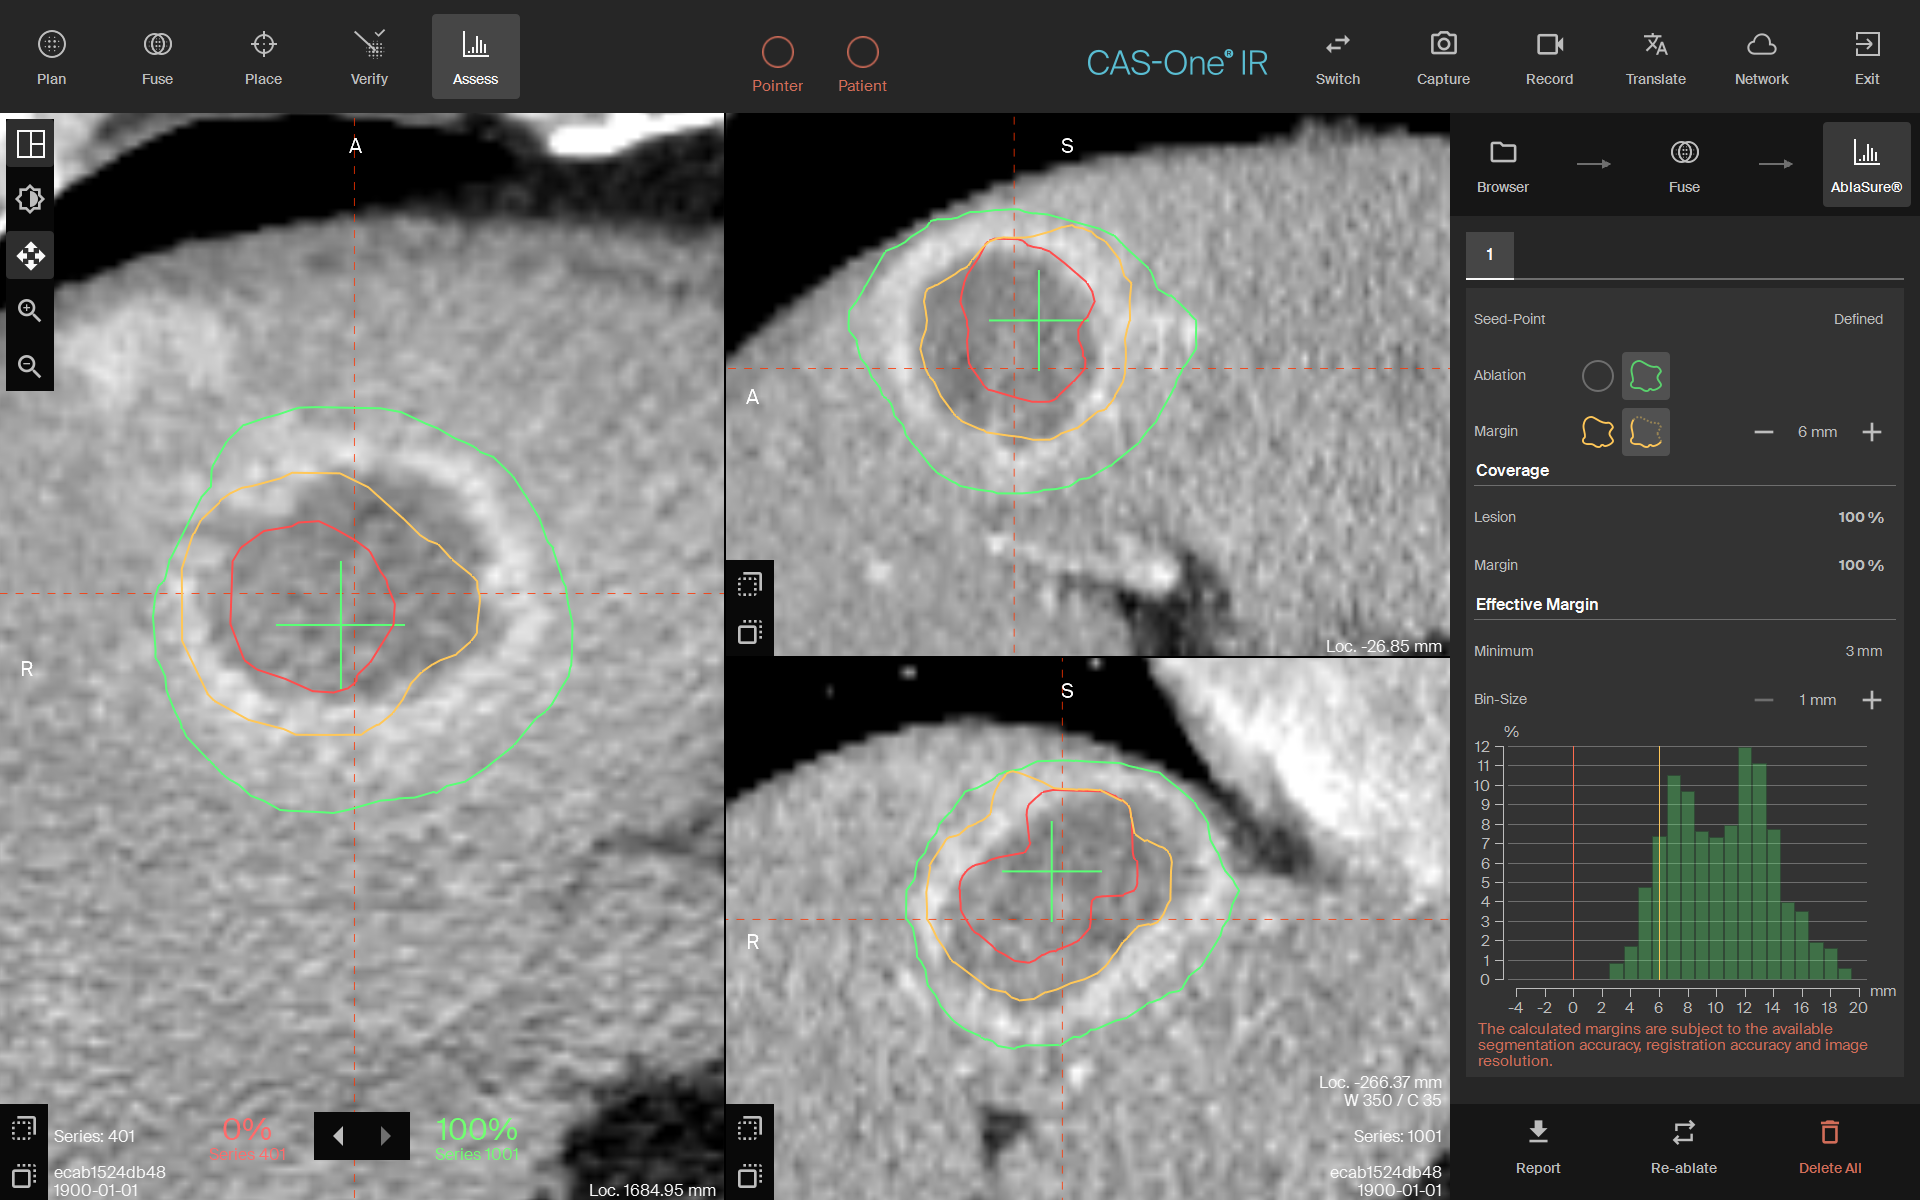

AblaSure showing a complete treatment of the lesion with a 6 mm safety margin

- CAS-One IR was used to properly plan the probes with a 10mm separation ensuring complete treatment volume, accurately place the probes including spacing, and assess the complete ablation of the lesion and margin

- AblaSure® analysis demonstrated what appeared to be complete coverage of the lesion and a minimal ablative margin of 6 mm.